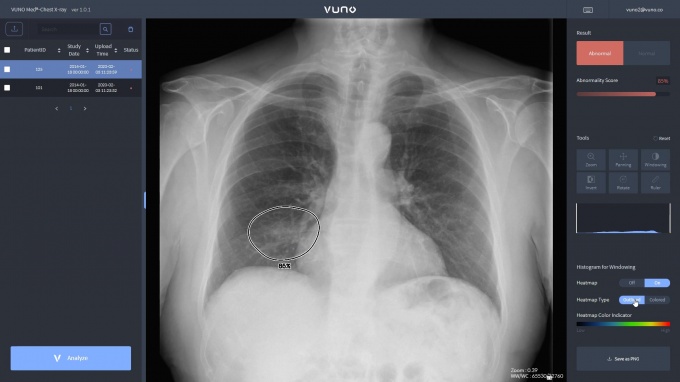

뷰노메드 체스트 엑스레이™는 폐렴 진단에 도움을 주는 주요 흉부 엑스레이 소견 3가지 ▲경화(consolidation) ▲간질성음영(interstitia lopacity) ▲흉막삼출(pleural effusion)을 비롯한 ▲결절(nodule) ▲기흉(pneumothorax) 등 총 5가지 소견을 검출하는 기능으로 임상시험을 통해 식품의약품안전처 허가를 받은 흉부 엑스레이 인공지능 솔루션이다.

허가받은 5가지 소견 및 질병에 대한 정상/비정상 분류 성능(AUROC)은 99%에 달한다.

뷰노 이예하 대표이사는 “뷰노메드 체스트 엑스레이™는 식약처 허가를 받은 제품 중 가장 많은 흉부 소견을 3초 이내 의심 병변과 함께 정확하게 검출한다”며 “이번 코로나19 대응 시 의료진 업무 경감 및 정확한 환자 분류 등에 도움을 줄 수 있을 것으로 기대된다”고 말했다.